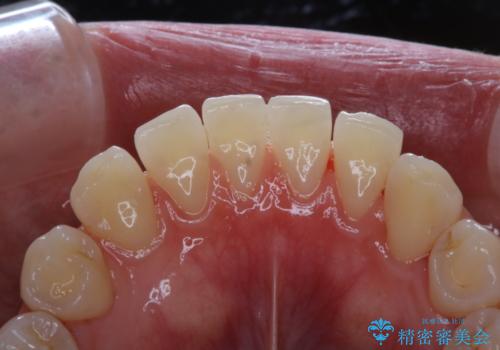

- これからインビザラインでのマウスピース矯正が始まるので、歯石取りをしてほしいとのことでした。

PMTC60分コースを行いました。